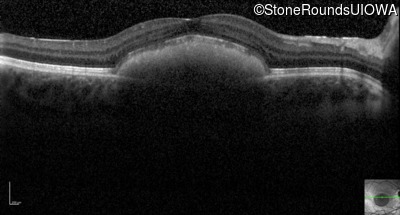

Optical Coherence Tomography - Right - 20/40 +2 sc

Exemplar / OCT Stack

Optical Coherence Tomography - Left - 20/30 sc